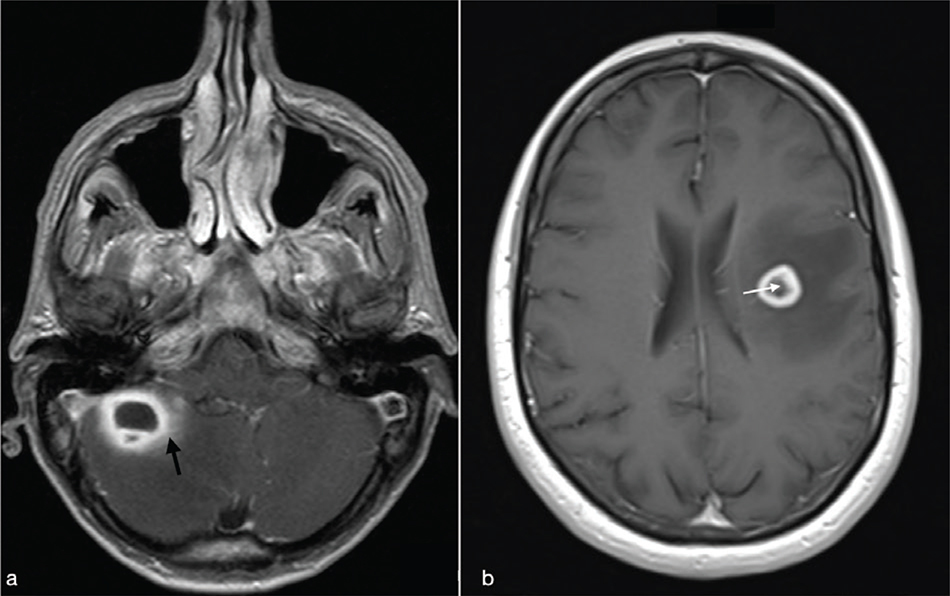

Cerebral toxoplasmosis is typical of immunocompromised patients. MRI shows multiple lesions in different stages of evolution typically located in the subcortical and periventricular white matter, in the basal ganglia and thalami. In particular, two signs are recognised as typical of toxoplasmosis: the “concentric” target sign (concentric alternating hypointense and hyperintense rims in T2w images), and the “eccentric” target sign (peripheral rim of enhancement and focal lateral eccentric enhancing nodule on T1w post-contrast) (Figure 16). On DWI, the centre of the toxoplasma abscess is seen to have ADC values higher than in pyogenic abscesses.22

FIG 16. Multiple Toxoplasma gondii Abscesses in a 45-Year-Old Immunocompromised Woman. T2w (a), T1+Gd (b, f), rCBV map (c), DWI (d) and ADC map (e). Multiple supratentorial brain abscesses in various stages of development with enhancing asymmetric nodules after Gd-injection (“eccentric target sign”) (arrows) can be observed (b, f). Note also the concentric alternating zones of hypo- and hyperintensities on T2w: “concentric target sign” (circle in a). Toxoplasma gondii abscesses typically do not show a core of restricted diffusion on DWI (asterisk in d) while low ADC values may be seen in the capsule (e).